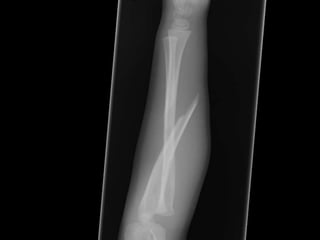

DIAGNOSTIC DIFFÉRENTIEL

Complète, déplacée

Incomplète, bois vert,

un cortex

Incomplète, torus,

aucun bris

Atelle ou Plâtre

AB (avant bras)

Réduction et Plâtre

Torus

• Buckle ou motte de beurre

• Fracture la plus fréquente en pédiatrie